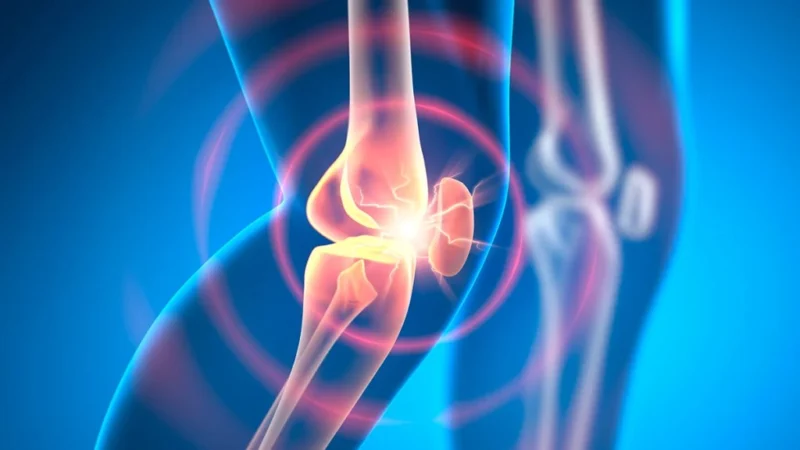

La osteoartritis es una de las enfermedades articulares más comunes y debilitantes del mundo. Afecta a millones de personas y, hasta ahora, no tiene cura. Sin embargo, una nueva investigación sugiere que un tratamiento experimental podría cambiar radicalmente este panorama en el futuro cercano.

Este avance es especialmente relevante si se considera que la osteoartritis progresa en varias etapas, desde un desgaste leve hasta la pérdida total de cartílago, donde el hueso queda expuesto y el dolor se intensifica. Actualmente, en fases avanzadas, las opciones suelen limitarse a cirugías invasivas como el reemplazo articular.